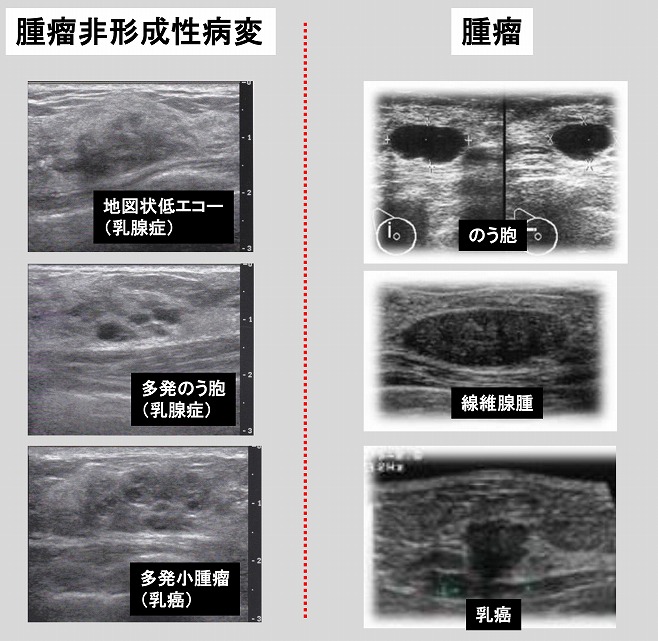

生理痛がひどい。卵巣嚢腫。チョコレート嚢胞のエコー像。子宮内膜症。 らぴゅたった

腫瘤非形成性病変